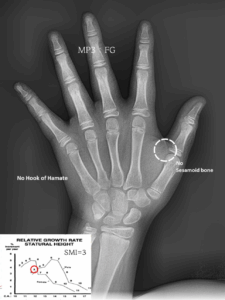

MARPE 악궁 확장을 통한 안면 골격 비대칭, 횡적 부조화(transverse discrepancy) 개선 과정

오늘은 진단이 다소 어려운 케이스인 '횡적 부조화'에 대한 내용을 설명해보려 합니다. ​ 전문적인 내용이라 살짝 이해하기 어려우실수도 있겠지만.. ​ 실제 케이스와 함께 최대한 쉽게 풀어서 설명드리도록 하겠습니다. 『불편하고 어딘가 불안정한…